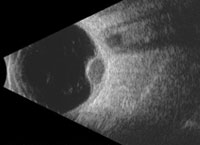

This ultrasound image shows a choroidal melanoma inside the eye as a round grey bump next to the shadow of the optic nerve.

A choroidal melanoma often appears as a dome-shaped dark tumor under the retina.